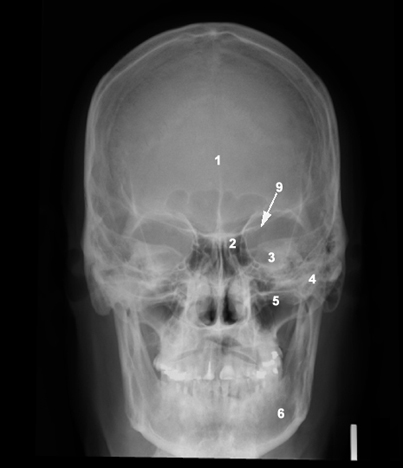

1: Frontal bone  2: Nasal bone  3: Inferior orbital fissure  4: Zygomatic  5: Maxilla

6: Mandible  9: Superior orbital fissure